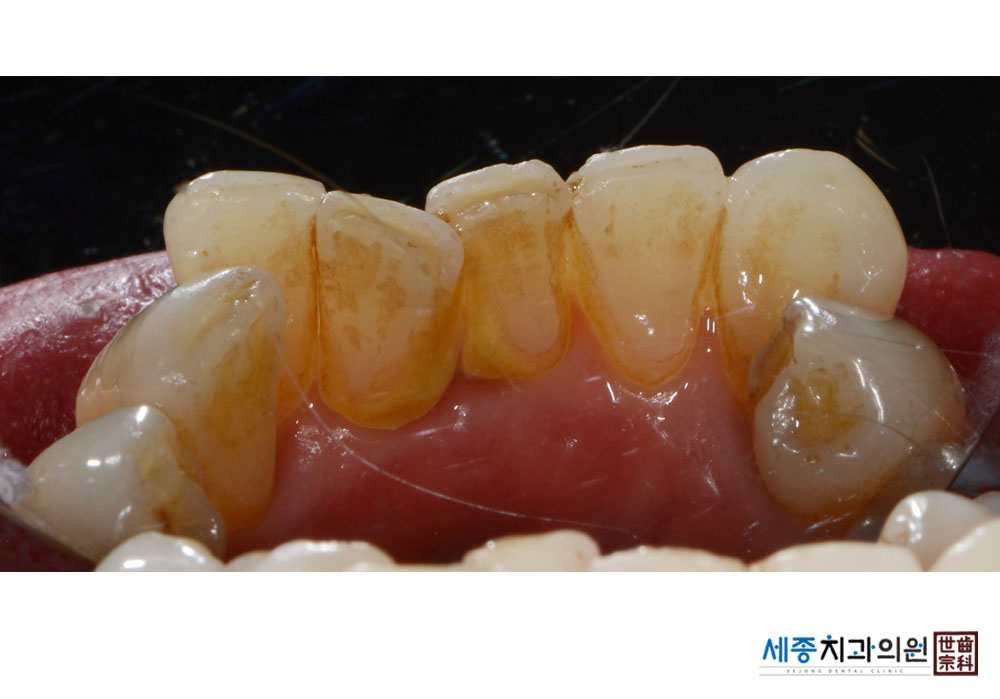

[스케일링] 치주질환 예방 스케일링

치료전 : 2021-05-03

가글마취&저주파 스켈러를 사용한 스케일링